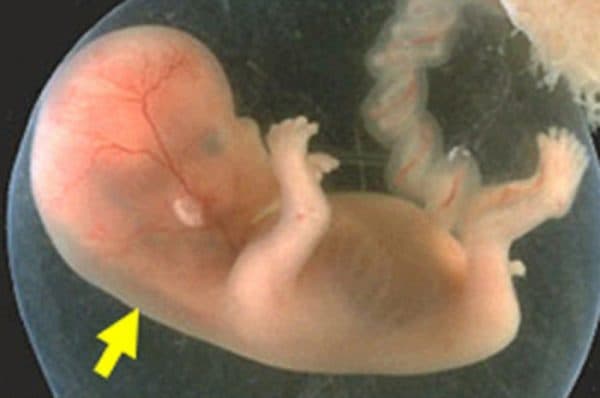

Vùng sau gáy của thai nhi có một khoảng sáng là nơi có sự kết tụ của một chất dịch gọi là độ mờ da gáy. Chỉ số này tại một số thời điểm cho biết nguy cơ bị dị tật down ở thai nhi. Vậy độ mờ da gáy bao nhiêu là tốt? Hãy cùng bài viết làm rõ vấn đề này.

Việc đo độ mờ da gáy là một trong những cách để kiểm tra nhằm phát hiện sớm hội chứng Down bởi những thai nhi này chất dịch ở gáy sẽ nhiều hơn bình thường khiến độ dày da gáy tăng lên. Tuy nhiên thời điểm thực hiện ảnh hưởng đến độ chính xác của xét nghiệm.

Dưới 11 tuần tuổi, độ mờ da gáy của thai nhi còn quá bé, khó xét nghiệm và cho kết quả không chính xác. Ngược lại trên 14 tuần, độ mờ da gáy đã trở về mức bình thường do đó việc đo chỉ số này không còn ý nghĩa.

Vì vậy đo độ mờ da gáy thông qua siêu âm được bác sĩ chỉ định trong khoảng tuổi của thai nhi là 11 – 13 tuần 6 ngày